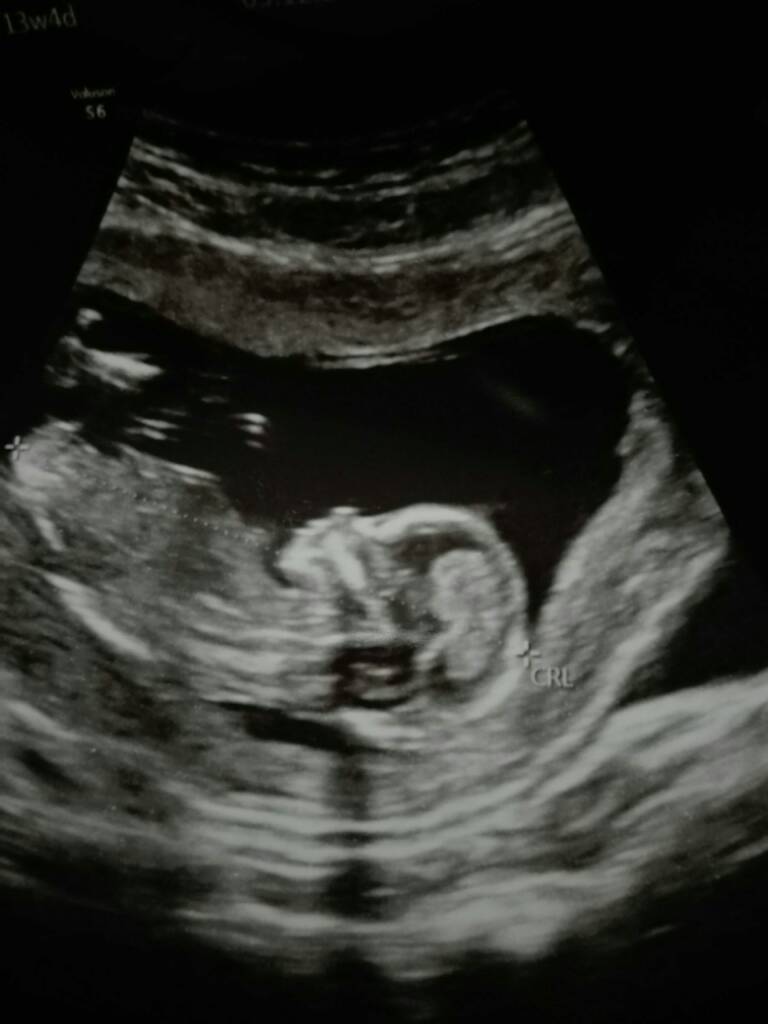

My juz po wizycie i według pani doktor z cala jej pewnoscia czekamy na dziewczynke [emoji7][emoji7]

Maluszek juz ma 7,41 cm a dzis 13+4.

Doktor długo robila mi dzis usg bo dzidza taka ruchliwa ze co probowala ją zlapac to uciekala [emoji87] uparciuch od malego [emoji14] tak fajnie podskakiwala, otwierala buzke, machala raczkami i kopala nozkami [emoji7]

Trzymam za kazda ze staraczek mocne kciuki [emoji110][emoji110] kazda z was ujrzy wreszcie taki widok, wiem ze czasami juz czlowiek w to nie wierzy ale to prawda !! [emoji176][emoji176][emoji176]

Wysylam ciazowe fluidy [emoji176][emoji176][emoji176][emoji176][emoji179][emoji179]Zobacz załącznik 921814